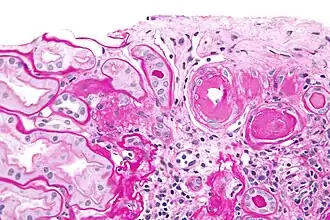

| Micrógrafo mostrando hialinose arterial renal - anel rosa á direita do centro. Coloração_ácido_periódico-Schiff. | |

Nos rins, como um resultado da hipertensão arterial benigna, a hialina (material homogêneo, amorfo rosa) se acumula na parede de pequenas artérias ou arteríolas, produzindo o espessamento de suas paredes e o estreitamento do lúmen — arteriosclerose hialina. A isquemia consequente produzirá atrofia tubular, fibrose intersticial, alterações glomerulares (glomérulos menores com graus diferentes de hialinização - da branda à esclerose dos glomérulos) e fibrose periglomerular. Em estágios avançados, a falha renal ocorrerá. Néfrons funcionais têm túbulos dilatados, frequentemente com cilindros urinários hialinos nos lúmens. Complicações adicionais frequentemente associadas com a nefropatia hipertensiva inclúem dano glomerular, resultando em proteinúria e hematúria.